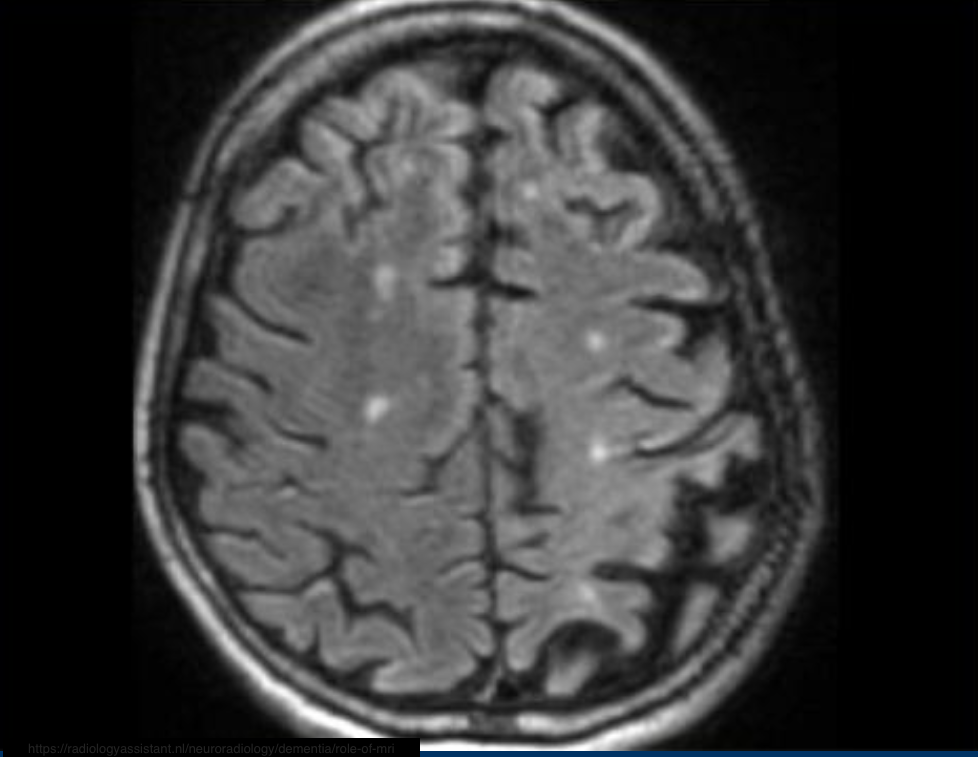

MRI shows asymmetric parietal cortical atrophy, sometimes with associated hyperintensity of the white matter on T2W images.

Axial FLAIR image shows striking asymmetric cortical parietal atrophy in a patient with CBD